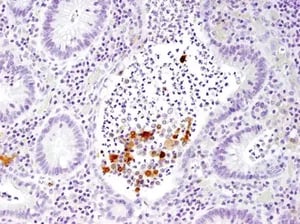

IHC analysis of paraffin-embedded human large intestine (chronic colitis of the colon) using IL-1 beta (3A6) Mouse Monoclonal Antibody #12242. |